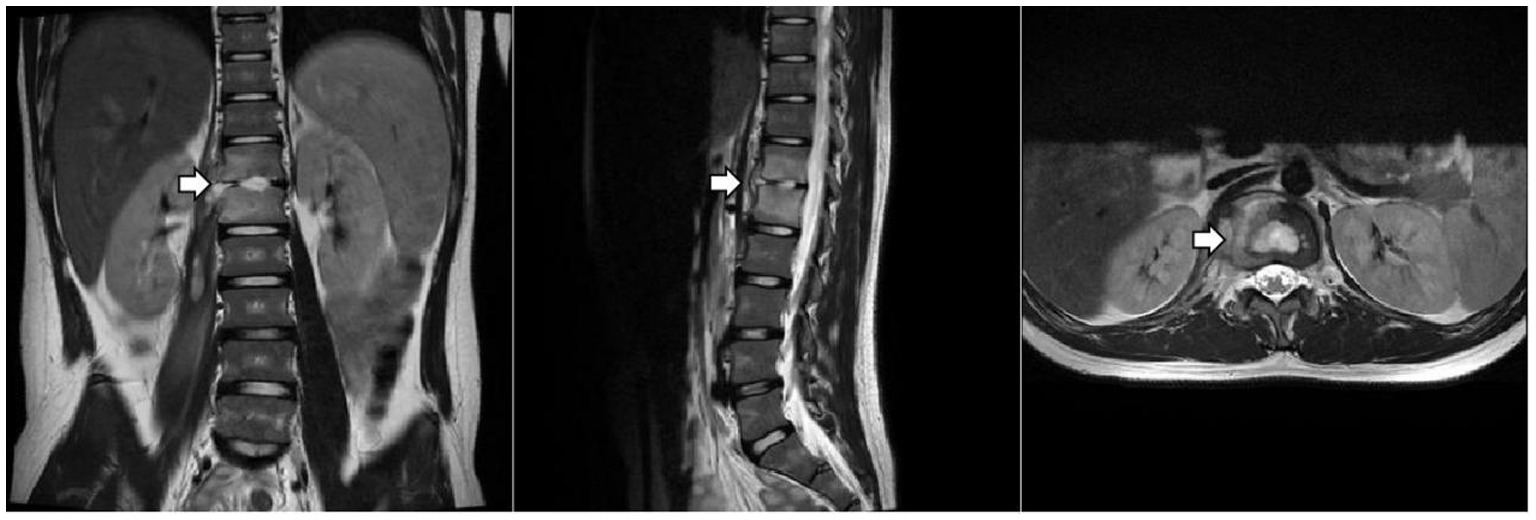

Culture and metagenomic next-generation sequencing (mNGS) of the surgically excised lesion identified Salmonella Dublin. Through multidisciplinary discussion involving the pediatric infectious diseases department, orthopedics department, radiology department, and pharmacy department, we concluded that the patient’s imaging findings were consistent with invasive non-typhoidal Salmonella infection and that the pathogen identified by both culture and mNGS was highly credible. Treatment with imipenem/cilastatin was continued according to antimicrobial sensitivity tests, while HRZE and vancomycin were discontinued. After two days of imipenem/cilastatin therapy, the patient had no further episodes of fever. After 10 days of imipenem/cilastatin therapy, follow-up thoracolumbar MRI (Figure 3) showed a reduction in bone marrow edema at T12-L1, as well as decreased lesions in the paraspinal soft tissue and the right psoas muscle. The patient was discharged after completing four weeks of treatment with imipenem/cilastatin and subsequently continued oral therapy with cefditoren pivoxil and levofloxacin for an additional four weeks. The patient attended follow-up visits at a local hospital. We learned from a phone call that he had recovered and resumed his studies (Timeline of the patient’s treatment see Figure 4).